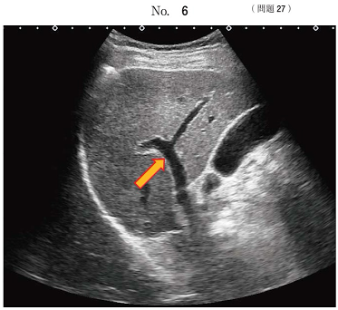

27. 健常者の右肋間走査の超音波像

- 矢印で示されるのは門脈 ( 右前枝 ) である

- 肝臓の右葉を中心に肝臓内の脈管と胆嚢が描出されている